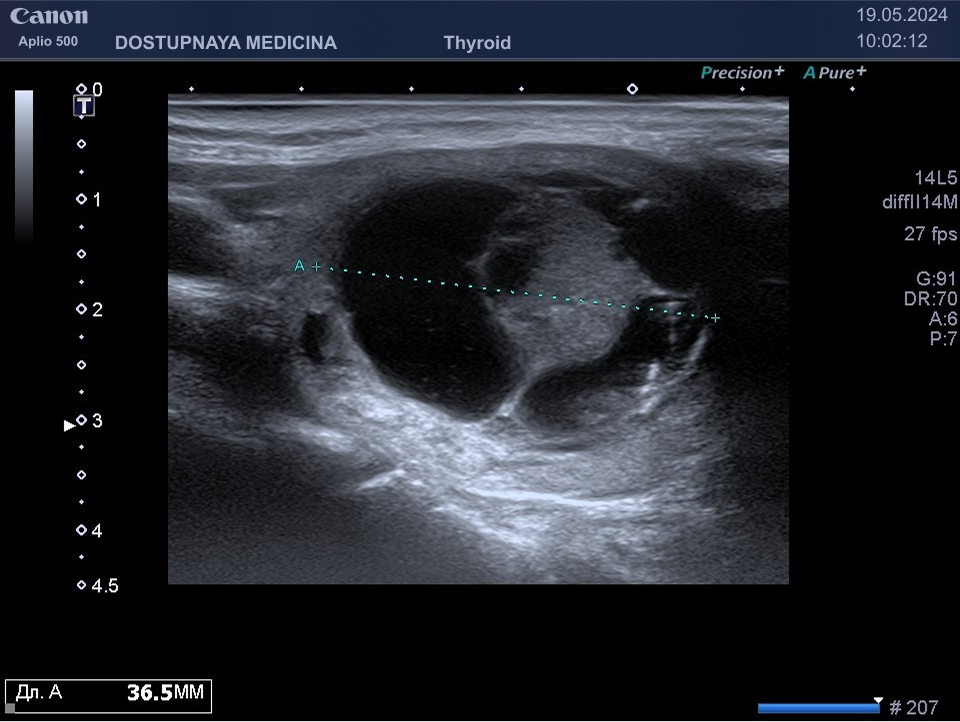

В ультразвуковой диагностике существует классификация образований щитовидной желзы по TIRADS, которая по различным критериям определяет степень онкоопастности того или ионого узла. При оценке учитывается эхоструткура образования ( кистозная, губчатая, солидная или солидно-кистозная), эхогенность ( анэхогенное, гиперэхогенное, гипоэхогенное), пространственная ориентация горизонтальная, вертикальная, неопределённая), контуры образования (ровные, дольчатые, зазубренные с острыми углами), наличие эхогенных включений( макрокальцинаты, микрокальцинаты, периферическая кольцевидная кальцификация). В зависимости от этих критериев выделяют различные категориии объёмных образований в щитовидной железе:

TIRADS 3 – низко подозрительное образование, требующие динамическое наблюдение и тонкоигольной биопсии при размерах узла больше 2.5 см.

TIRADS 4 – умеренно подозрительное образование, требующие динамическое наблюдение и тонкоигольной биопсии при размерах узла больше 1.5 см.

TIRADS 5 – высоко подозрительное образование, требующие динамическое наблюдение и тонкоигольной биопсии при размерах узла больше 1 см.

Большинство узловых образований в щитовидной железе не нуждаются в лечении и требуют лишь наблюдения путём повторного ультразвуковых исследований.

При подозрении на озлокачествление и увеличении узла в размерах требуется тонкоигольная пункционная биопсия с полседующим цитологическим исследованием, полученного материала.